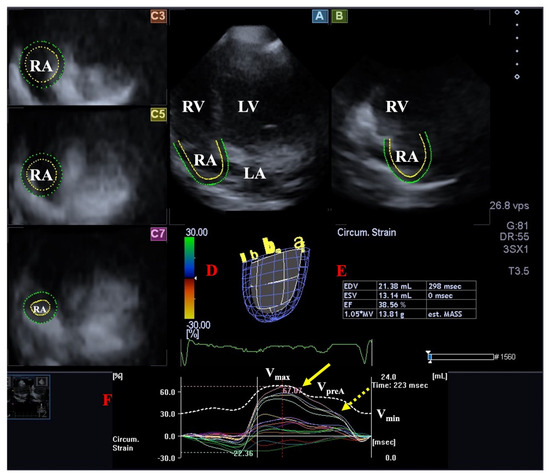

- Nemes, A.; Domsik, P.; Kalapos, A.; Gavallér, H.; Oszlánczi, M.; Forster, T. Right atrial deformation analysis in isolated left ventricular noncompaction–insights from the three-dimensional speckle tracking echocardiographic MAGYAR-Path Study. Rev. Port. Cardiol. 2016, 35, 515–521. [Google Scholar] [CrossRef]

| Right atrium | RA volumes and certain stroke volumes were increased without RA strain abnormalities. | [19] * | 13 |